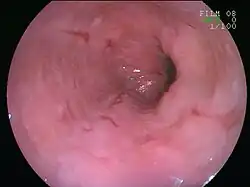

![]() | |

| An esophageal ulcer visualized by esophagoscopy: the reddened area at 10 o'clock on the surface of the mucosa. | |